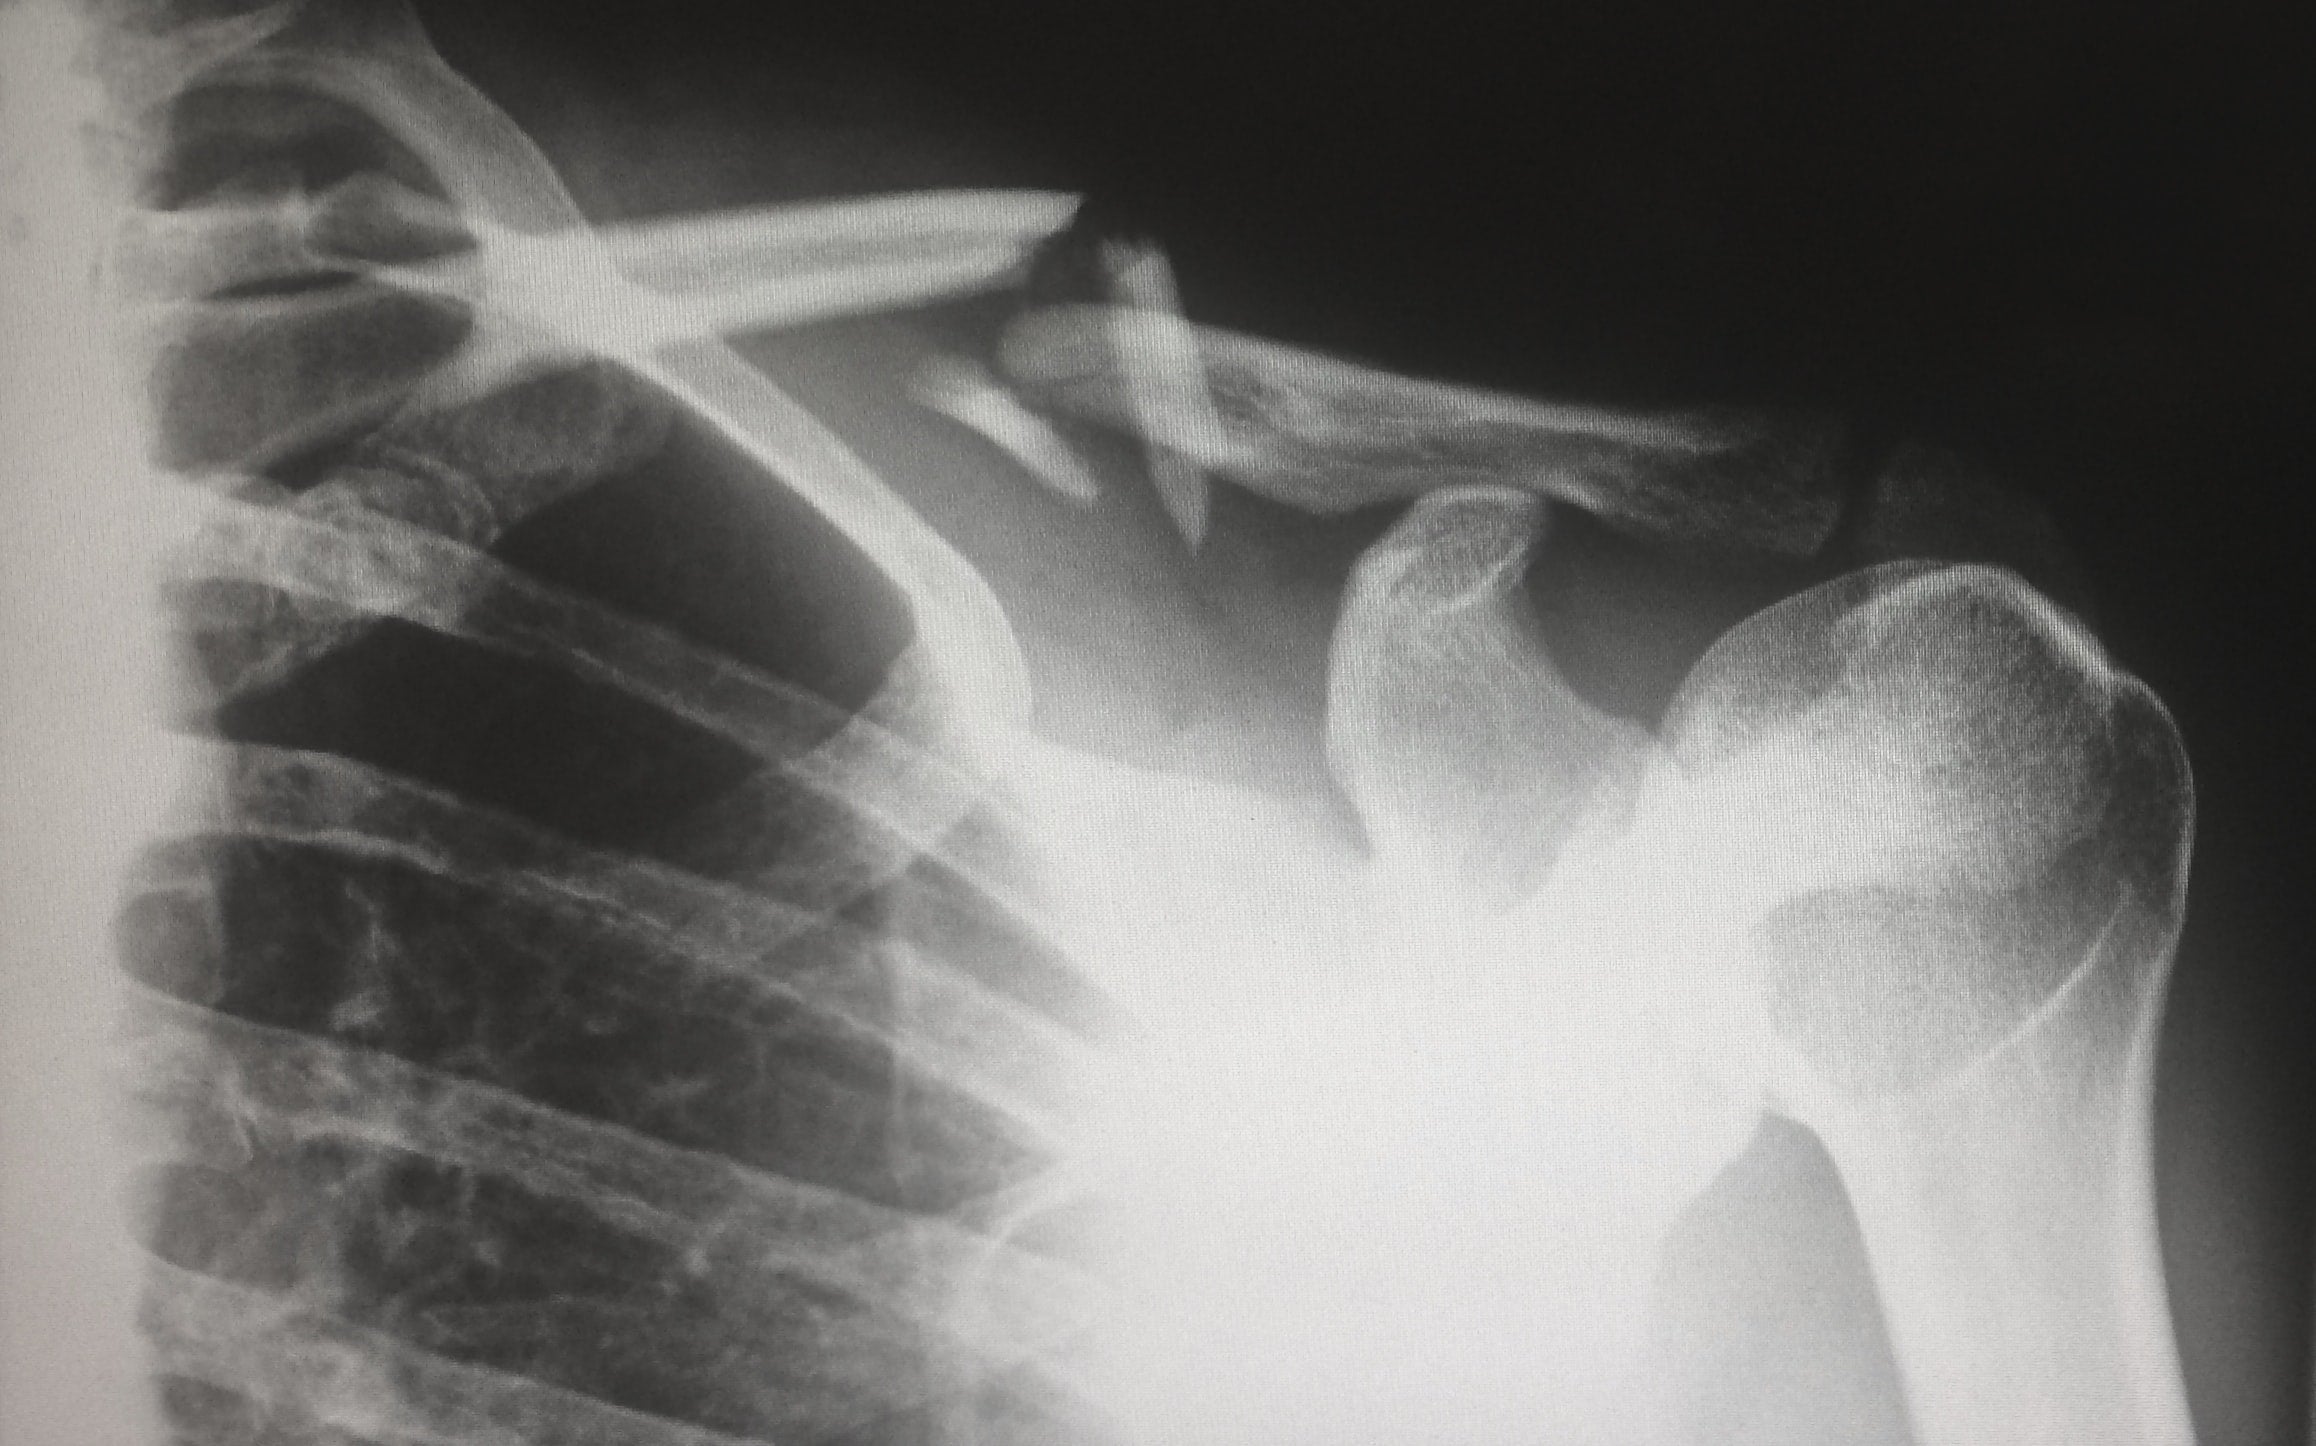

Porfintu.com: la plataforma que guia les dones per conviure amb la osteoporosi i la menopausa

A la secció de salut en femení que fem amb l’Associació Hera, avui ens acompanya amb Mireia Serra, especialista en osteoporosi i guardonada als Premis Hera 2023 en l’àmbit d’emprenedoria per la seva tasca divulgadora. La Mireia ha creat Porfintu.com, una plataforma amb cursos i classes online pensats per ajudar les dones a guanyar força, mobilitat i confiança en les dones diagnosticades amb osteoporosi i durant l’etapa de la menopausa. A La Ciutat Lleida parlem amb la Miriea d’exercici segur, de prevenció, de bons hàbits alimentaris que poden marcar una diferència real en la qualitat de vida.